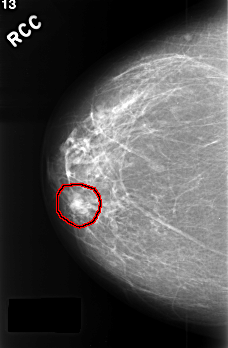

FILE: C_0390_1.RIGHT_CC.OVERLAY

TOTAL_ABNORMALITIES 1

ABNORMALITY 1

LESION_TYPE MASS SHAPE LOBULATED MARGINS CIRCUMSCRIBED

ASSESSMENT 4

SUBTLETY 5

PATHOLOGY BENIGN

TOTAL_OUTLINES 1

BOUNDARY